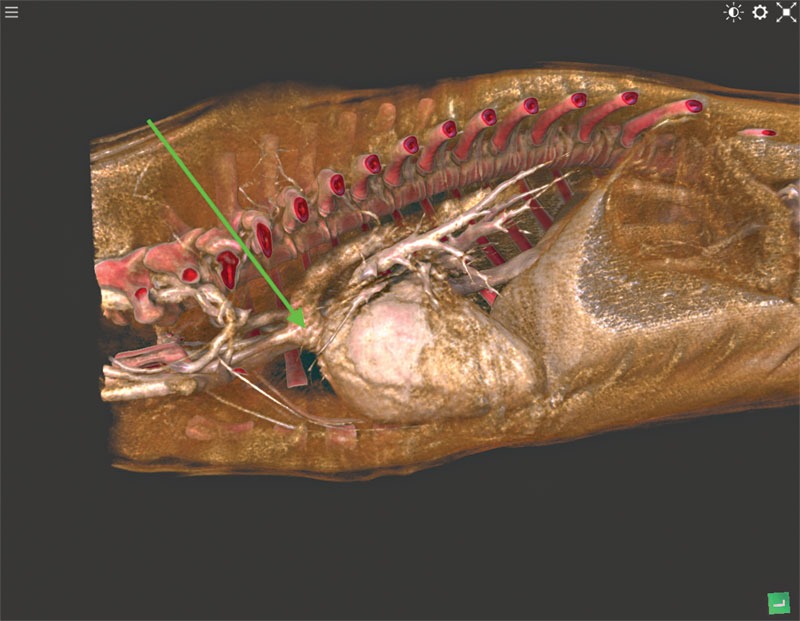

Shunts are caused by a birth defect when a puppy is born with too many vessels formed in or around the liver. Blood from the portal system abnormally detours around the liver and instead returns to the heart by entering the systemic venous drainage in a number of different patterns (Figures 1A and 1B).

Black-and-white 3D images of a portosystemic shunt (1A) and a splenoazygos shunt (1B). Photo courtesy Imaginalis

Another condition that can be seen in puppies is a PRAA, also known as a vascular ring anomaly (Figure 2). Birth defects also cause these and result in partial or complete rings forming around and squeezing the esophagus, trachea, or sometimes both. As the puppy grows, this issue becomes more apparent.

Figure 2. Evidence of a persistent right aortic arch (PRAA) in a one-month-old poodle puppy. Photo courtesy Imaginalis

This condition is the most disruptive of the three. An example of its impact was seen when a one-month-old poodle puppy was brought in because it was vomiting after every meal and was noticeably underweight compared to the rest of the litter. Diagnostic imaging found compression on her trachea and esophagus that would continue to impact her health. The condition would likely prove fatal if left untreated.

For example, after a veterinarian detected a PRAA on an HDVI CT scanner (Figure 3) and surgically removed it from a one-month-old poodle puppy, the patient caught up to the rest of the litter and is now living a normal life.

Figure 3. A PRAA detected by an HDVI CT scanner. Photo courtesy Imaginalis